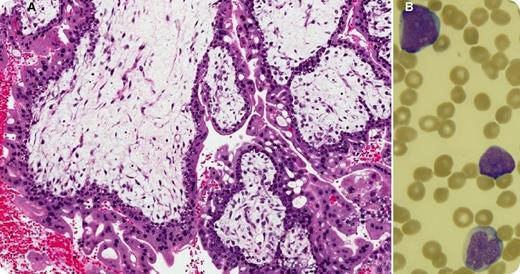

Thirteen months after the successful treatment of a persistent complete hydatidiform mole (panel A: diffusely hydropic, grape-like chorionic villi surrounded by hyperplastic atypical trophoblast), a 27-year-old woman with no family history of cancer presented with fatigue, sore throat, and petechiae for a few weeks. Her prior treatment included a single cycle of single-agent methotrexate that was followed, because of a further increase in human chorionic gonadotropin, by 9 biweekly cycles of etoposide, methotrexate, dactinomycin, cyclophosphamide, and vincristine (EMA/CO regimen). Blood work at this time showed hemoglobin, 10.9 g/dL; white blood cells, 41.4 × 109/L; platelets, 15 × 109/L; and 60% blasts (panel B). The bone marrow was packed (95% cellularity) with immature myeloid cells that stained positively for CD13, CD33, CD34, and myeloperoxidase and negatively for CD3. Cytogenetic analysis revealed a core-binding factor β rearrangement at 16q22. A diagnosis of therapy-related acute myeloid leukemia (t-AML) was established.